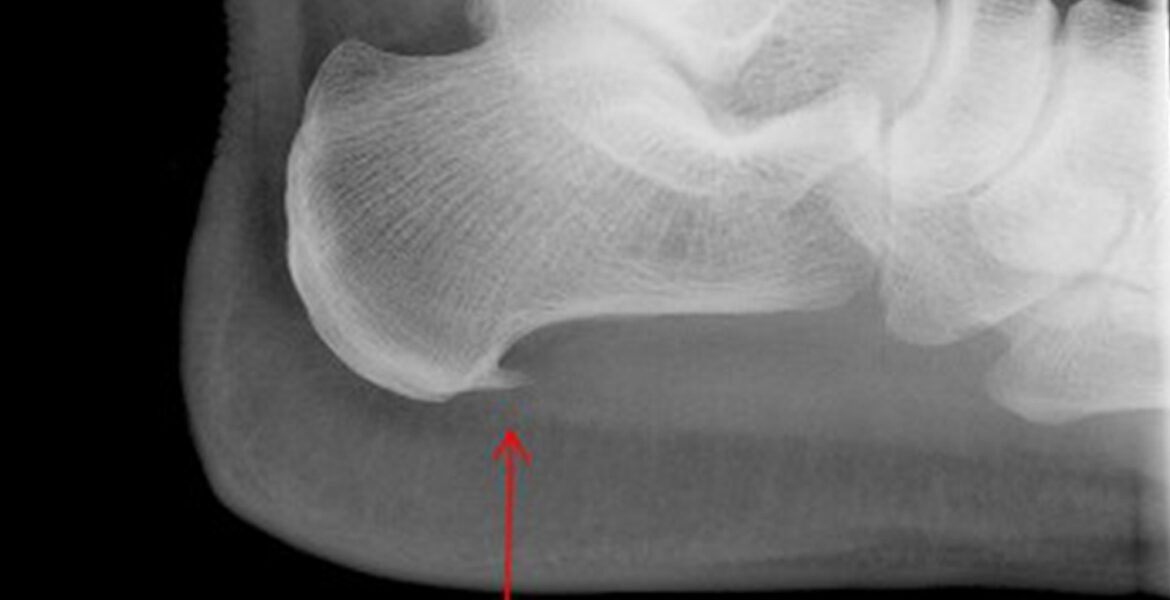

Plantar Fasciitis causes pain under your heel. It can be unpredictable and strike indiscriminately — it seems mine was triggered by wearing sneakers for a couple of days in a row.  I had just bought TWO pairs of these cute converse style lace ups from Kurt Geiger thinking how stylish and sensible (good for my bad back and achy knees …that’s a whole other story).

FasciitisIt is easy to diagnose and GPs are familiar with the classic symptoms.  Mainly a hot flash of pain as you take your first steps of the day across the bedroom. The pain re occurs during the day particularly if you sit for a while and then start walking again.

Currently every morning when I get-out of bed my right foot has a really sharp unpleasant pain underneath by the heel as I put my weight on it.  Now I have to wear orthotics inside my shoes, visit a physiotherapist and do exercises.  If I’m diligent it should improve. Although I gather that there isn’t a cure for this condition.  I’m fortunate that I have medical insurance with Bupa and so I managed to get to see a top foot and ankle doctor Mr Martin Klinke from The London Foot & Ankle Centre.  Mr Klinke was kind and thorough. As part of his care I also visited Rina Bimbashi a top Podiatrist also part of The London Foot & Ankle Centre.

Apparently this is a very common complaint and guess what, if you are overweight you will be more susceptible to getting it.